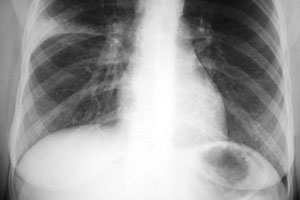

Пневмония диагностируется рентгенологически, если её не видно на снимках - её нет. Учитывая анамнез и гнойный характер мокроты, вероятна вторичная по отношению к банальной вирусной инфекции реактивация (поли-? мульти-?)резистентного вследствие повторяющихся с детских лет курсов АБ-терапии стафилококка, который благополучно живёт с Вами большую часть жизни (хотя возможна и другая бактериальная флора). Санация необходима, так как дальше обострения будут лечиться только хуже; крайне желателен бакпосев мокроты с определением чувствительности возбудителя, который будет выделен, к антибиотикам, при этом нужно убедиться, что конкретная лаборатория имеет возможность использовать диски с достаточным количеством современных препаратов.

Затяжна пневмонія – пневмонічний процес, який не розв’язується протягом 4-6 тижнів від початку хвороби.